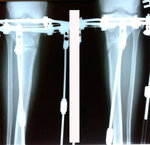

Исходник - 48 лет.

Диагноз: варусная формация голеней.

Дата операции - 17.10.2019г.

на фиксации